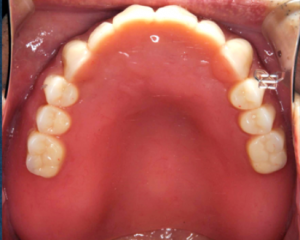

全顎治療の方が先日ようやく終わった。左写真が術前、右写真が術後である。コロナのせいで治療間隔があいてしまい予定よりも3か月遅れである。患者さんは職場が4月から変わり大手町から離れてしまったのとコロナのダブルパンチを食らってしまった。来院される際には半日休みをとったとのことだったので、まとめてできるところはまとめて2時間以上のアポをとって行った。ミスは許されないプレッシャーもあった。自分が若いころにはどうやって治療していいか皆目見当がつかないようなぐちゃぐちゃな口腔内だったが、今はシンラシステムという咬合診断装置があるので、こうしたケースにも対応できる。というかむしろ歓迎である。創造力が掻き立てられるのだ。仮歯の時におきたトラブルも参考にして最終的な材質を選択した。見た目よりも強度が必要なケースだった。術後の租借能力検査、咬合力検査では基準値以上の値を示し、まずまずの咀嚼器を作れたのではないかと自負したいところだが、本当の勝負はこれからである。長期間壊れないように祈るばかりである。